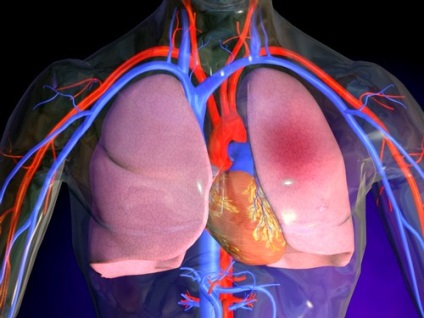

edem pulmonar apare ca urmare a expunerii la un factor extern care afectează acumularea de lichid seros in alveolele, ceea ce duce la o perturbare a schimbului de dioxid de carbon și oxigen. Se poate umfla cu ușurință la stagnarea sângelui sau deteriorarea structurilor pulmonare.

Alveolele care plamanii sunt pungi subtiri acoperite cu mici vase de sange. Dacă apare edemul, acestea sunt umplute cu lichid, ceea ce duce la o perturbare a corpului si oxigen schimbul cu dioxidul de carbon. Rezultatul este o lipsa de oxigen a tuturor organelor.

În boli congenitale sau dobândite ale inimii și a vaselor de sânge, nu este exclus posibilitatea dezvoltării de edem în plămâni. Motivul pentru care acest lucru devine insuficientă circulație a sângelui, ceea ce duce la o creștere a presiunii. În cazul în care sângele pentru o lungă perioadă de timp este în pereții vaselor de sânge, plasmă sale începe să pătrundă în alveolele și se acumulează acolo.